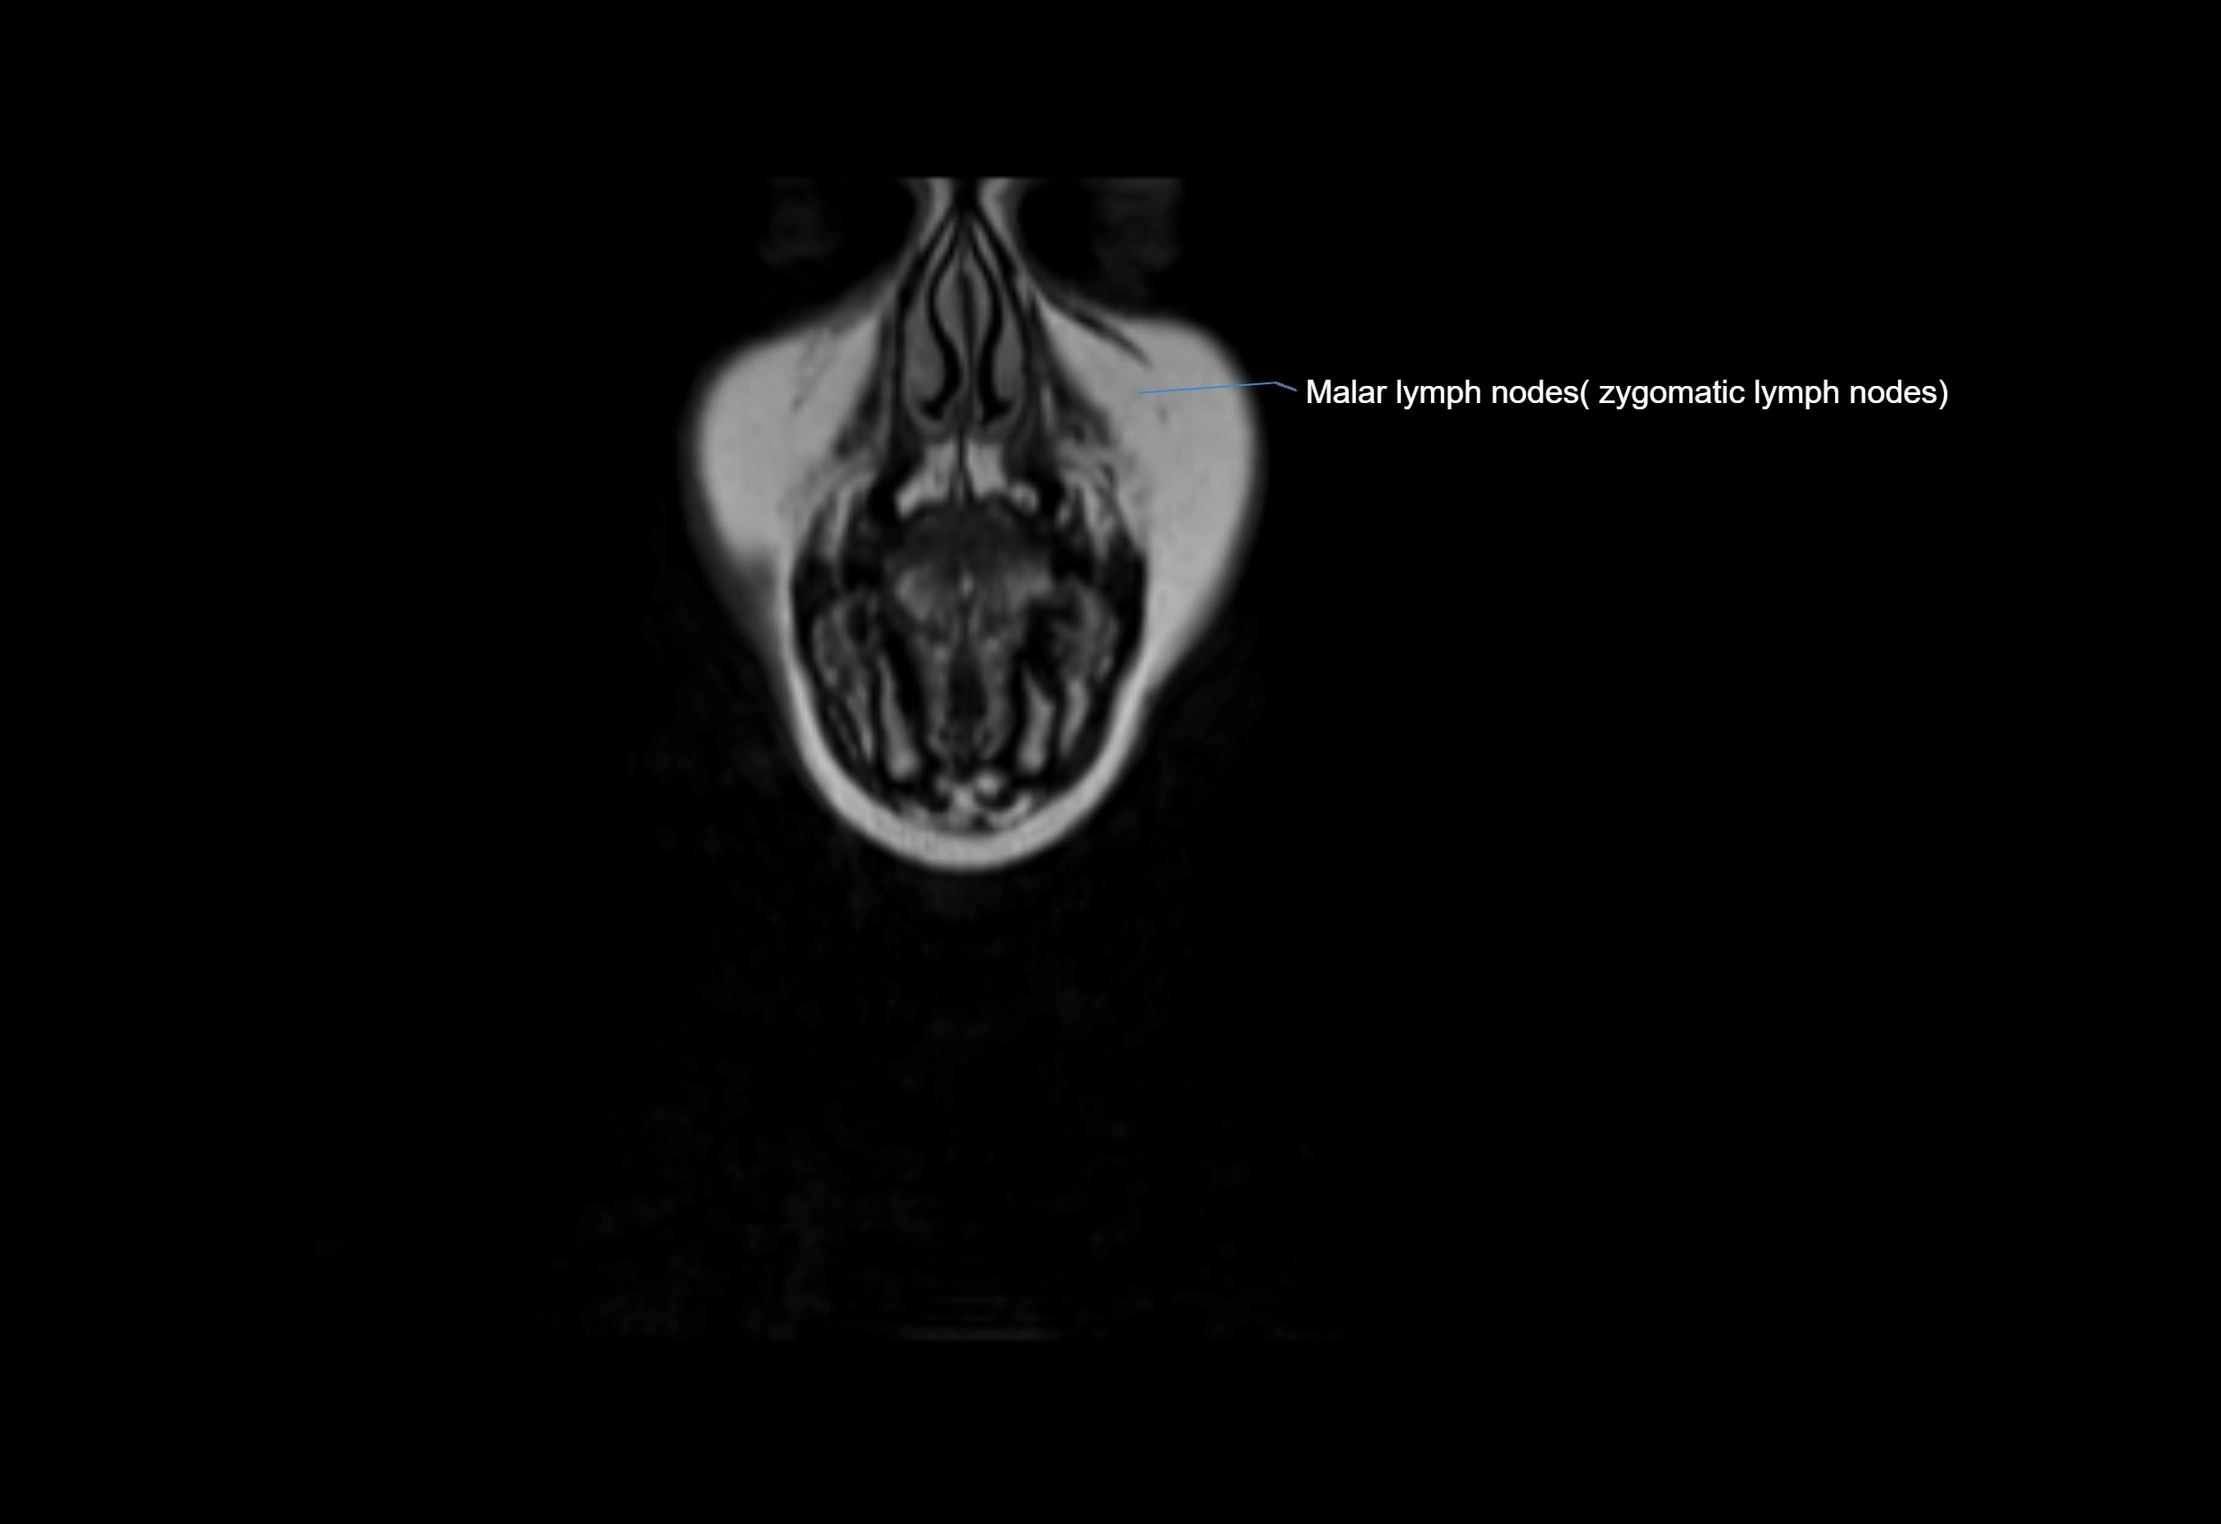

MRI Appearance

T1-weighted images:

• Normal accessory nodes appear as small, oval hypointense to intermediate signal structures within subcutaneous fat

• Surrounded by hyperintense fat, enhancing contrast for visualization

• Pathological nodes may appear enlarged or rounded, sometimes with cortical thickening

T2-weighted images:

• Nodes show intermediate signal, with surrounding fat bright

• Useful for detecting edema, inflammation, or infiltration

• Fatty hilum may appear slightly hyperintense relative to cortex

MRI images